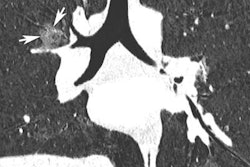

The team focused on five indication-based single-phase CT protocols: head for cerebral hemorrhage; thorax for pulmonary nodules/pneumonia; abdomen-pelvis for acute abdomen; low-dose pulmonary angiogram for pulmonary embolism; and low-dose renal colic for urolithiasis.